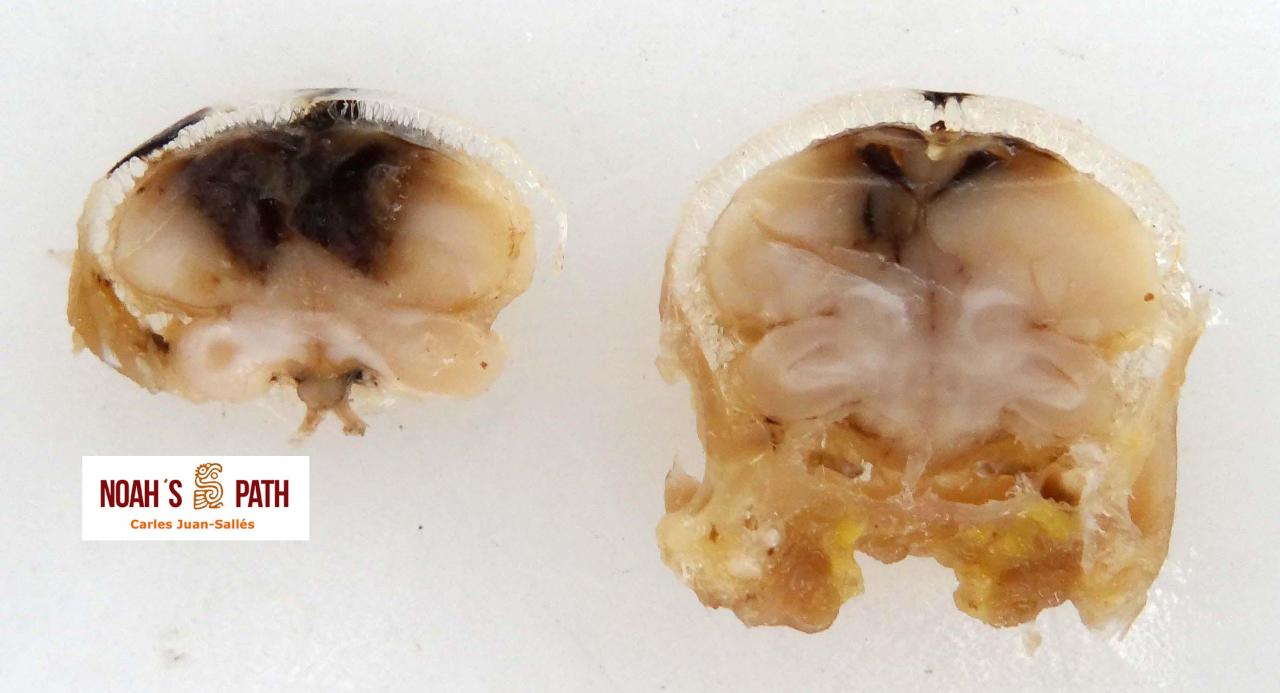

El examen post mortem ofrece una oportunidad única de acceso a todos los tejidos del paciente para diagnóstico de las causas de enfermedad y muerte, y por lo tanto es esencial para medicina preventiva y curativa en grupos de animales, seguimiento de casos, estudios sobre enfermedades, control de zoonosis, medicina de la conservación, y patología forense. En Noah's Path pensamos que un examen post mortem de este tipo de fauna debería ser realizado siempre que sea posible por patólogas/os especializadas/os con el fin de obtener el máximo de información y obtener las muestras más adecuadas.